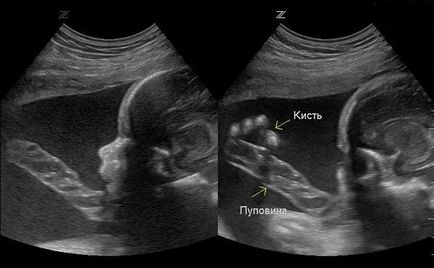

Fotografii cu ultrasunete la 32 de săptămâni de sarcină

Dacă întrebarea este despre entanglement din cordonul ombilical, se recomandă deținerea trei suplimentare sau cu ultrasunete cu patru dimensiuni.